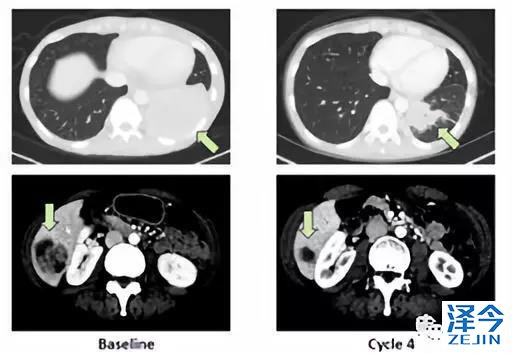

还有安娜,她是一位45岁的晚期肺癌病人,肿瘤有NTRK1-SQSTM1突变。同样是在化疗无效的情况下,经过我4个周期的治疗,她的肿瘤几乎看不到了。